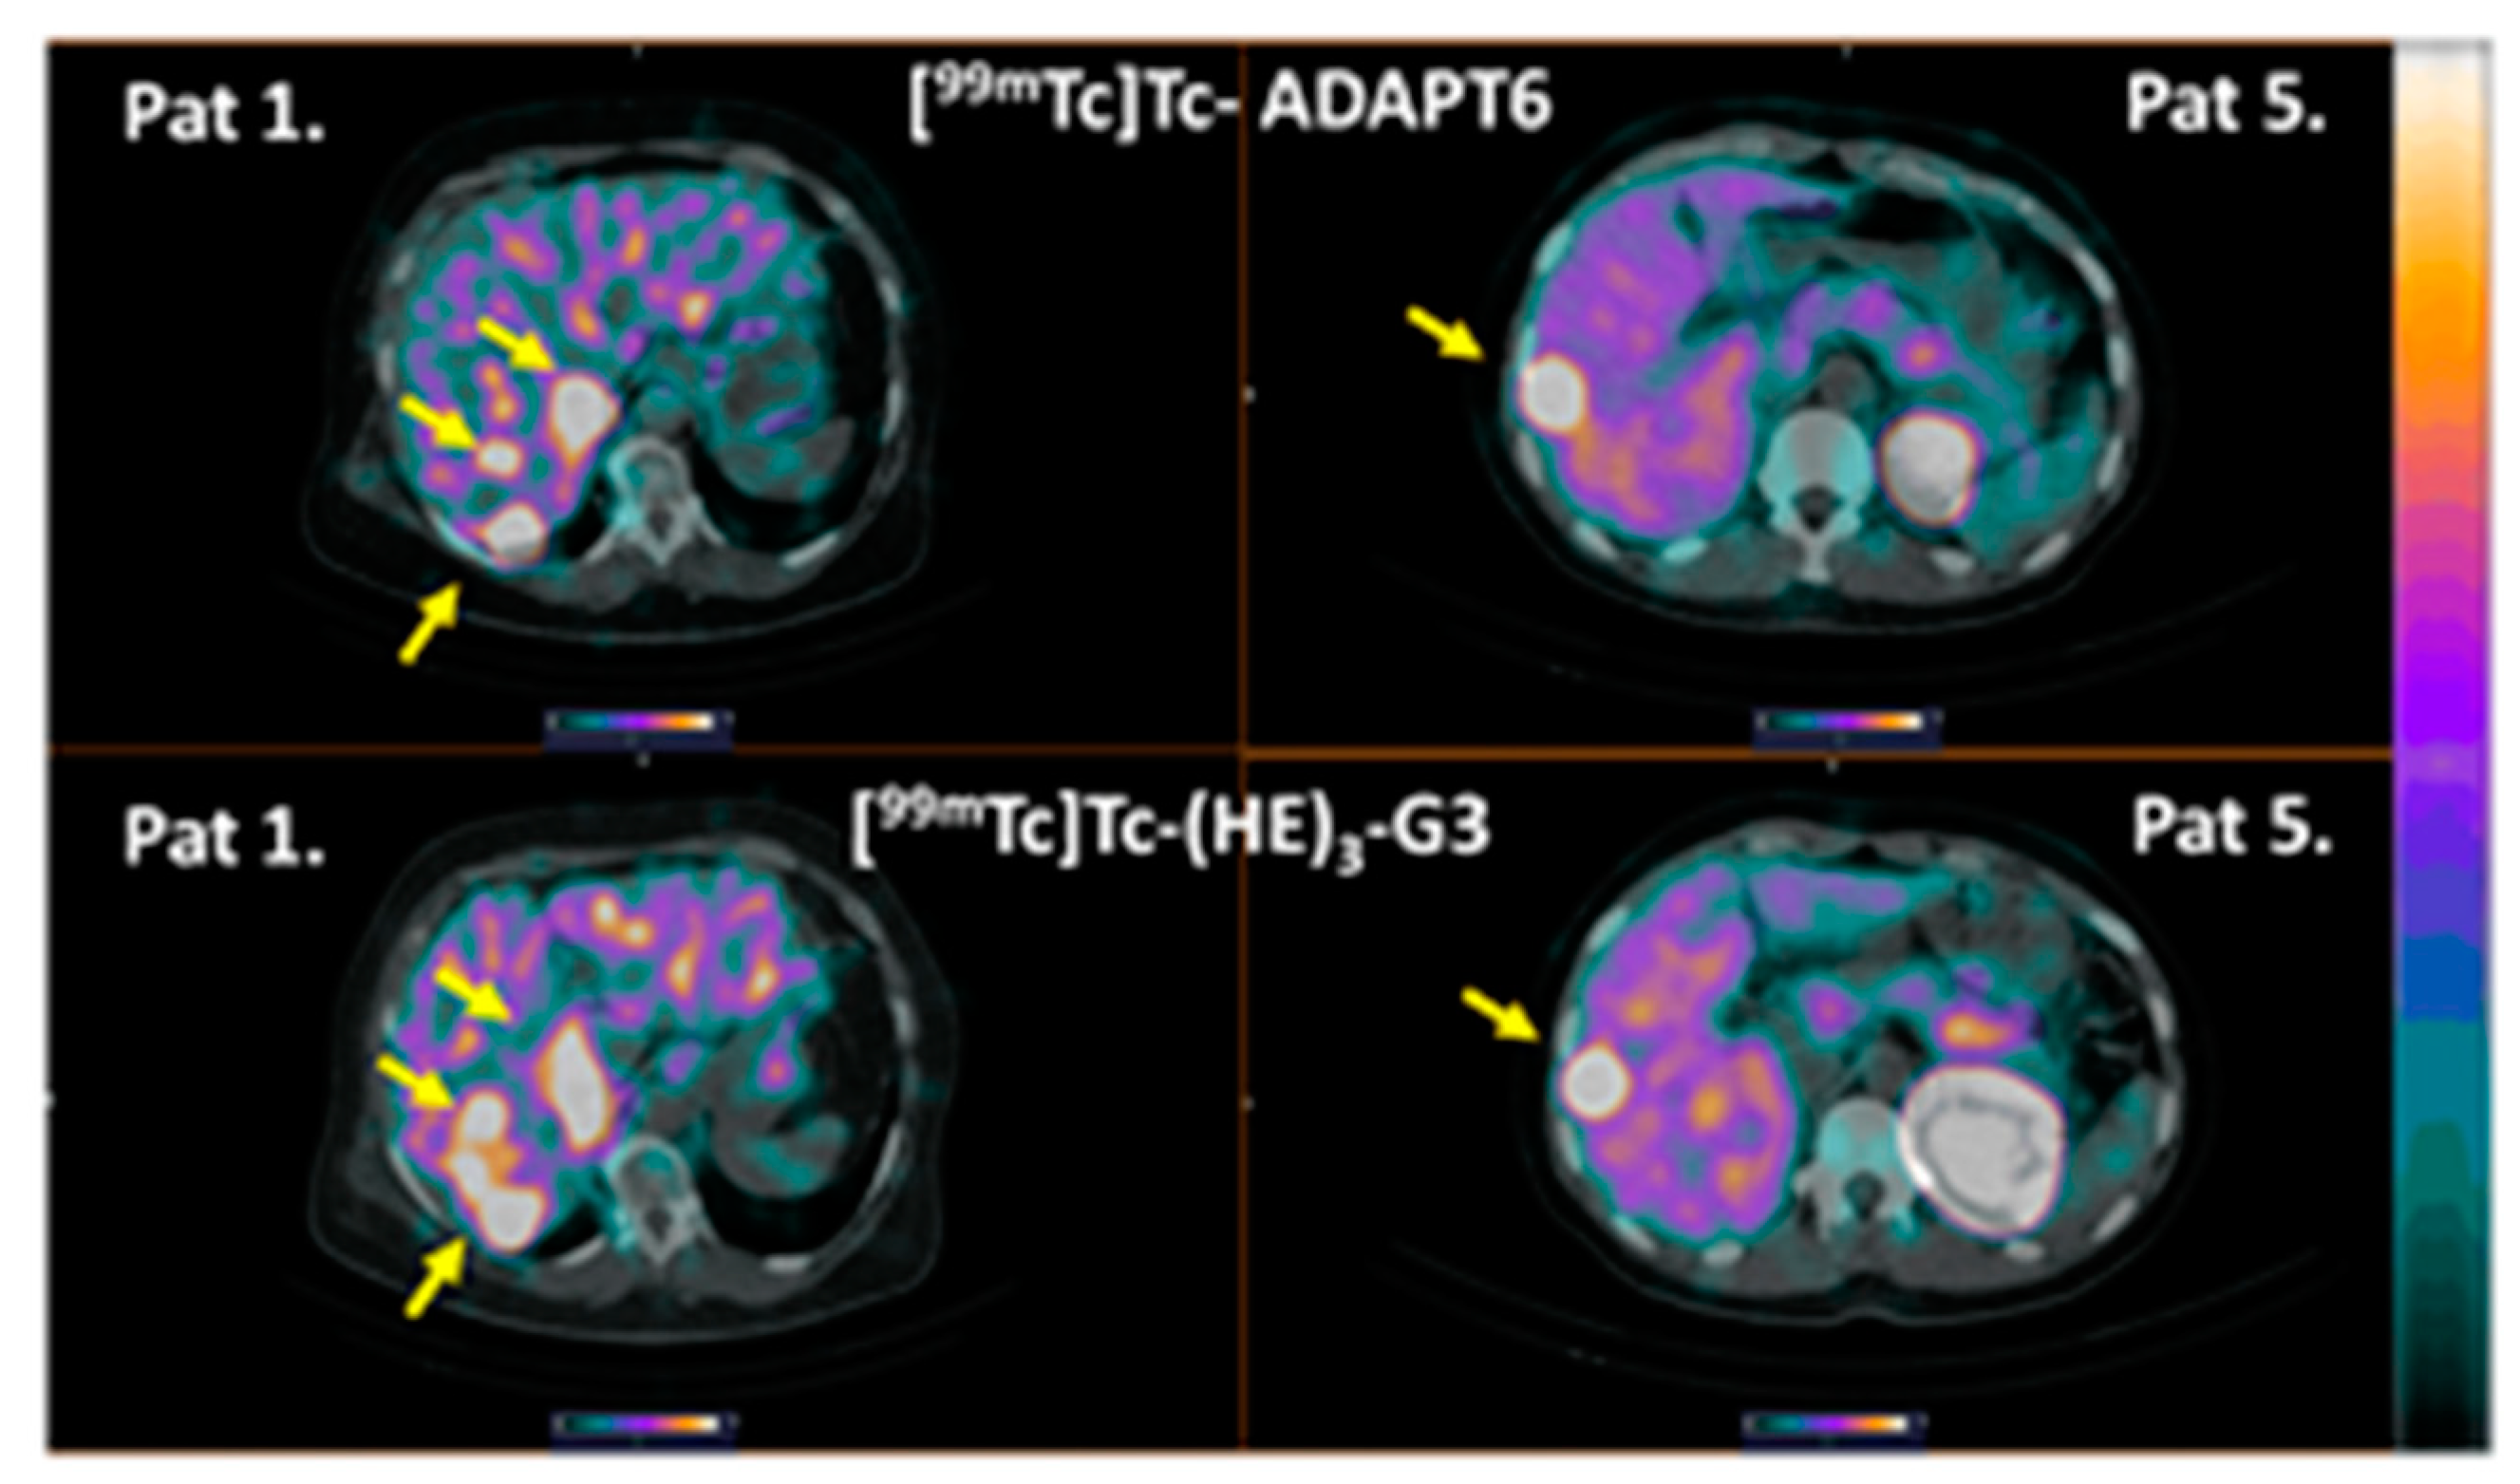

3. Results

4. Discussion